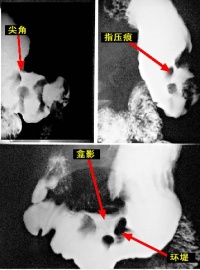

进展期胃癌Ⅱ型的X线常表现为不规则龛影,多成半月形,外缘平直,内缘不整齐而有多个尖角,龛影位于胃轮廓之内,龛影外围绕以宽窄不等的透明带环堤,轮廓不规则但锐利,其中常见结节状或指压状充盈缺损,以上表现称之为半月综合征。伴有粘膜纠集但中断于环堤之外。